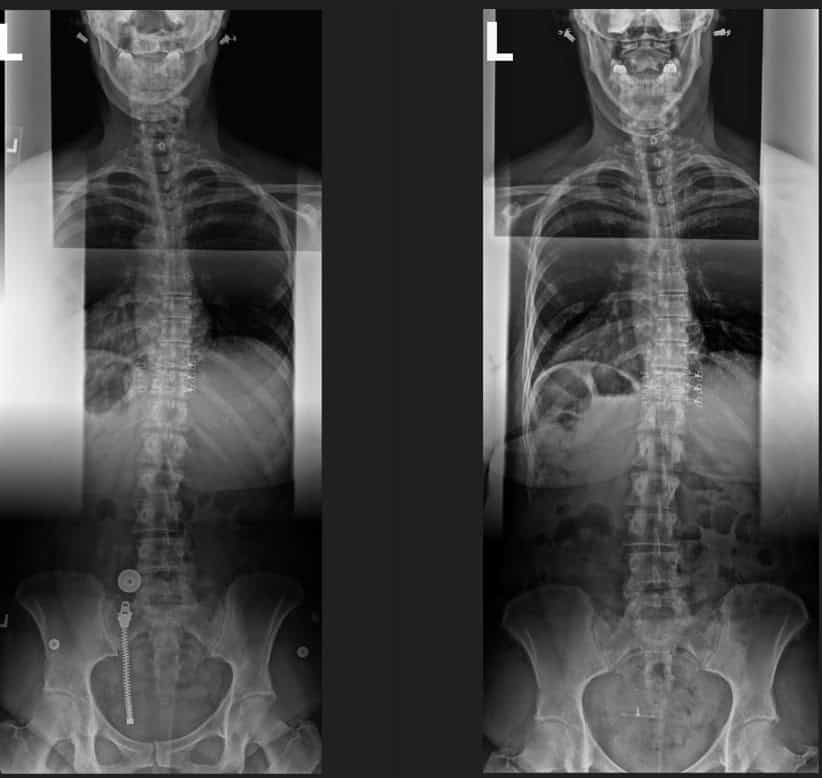

Pre & Post Scan